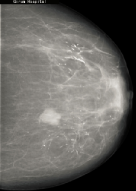

The dataset was mainly collected from St.Gebriel Hospital, Grum Hospital, Betezatha Hospital, Korean Hospital, Kadisco Hospital and Pioneer Diagnostic. The MG images were collected with their document reports that show the screening and diagnosis results of the patients. The documents report results were based on the pathology confirmation and Breast Imaging-Reporting and Data System (BI-RADS). More than 5000 x-ray mammogram images that were diagnosed between 2016 and 2018 as shown in table 1 were collected and some of the samples are shown in figure 1. This work considered only the mass abnormality from the collected MG images, that is 1588 full mammogram images which have mass abnormality and annotated by professional radiologists using the labelMe Russell et al. (2008) annotation tool. The dataset was divided into training (80%), validation (10%), and testing (10%).

Refer to caption

(a)

(b)

(c)

Figure 1: Sample of MG images during acquisition stage. The mammogram images are from different mammography x-ray sources: (a) from Girum Hospital, (b) from Pioneer Diagnostic Center, and (c) from St. Gebriel Hopital.